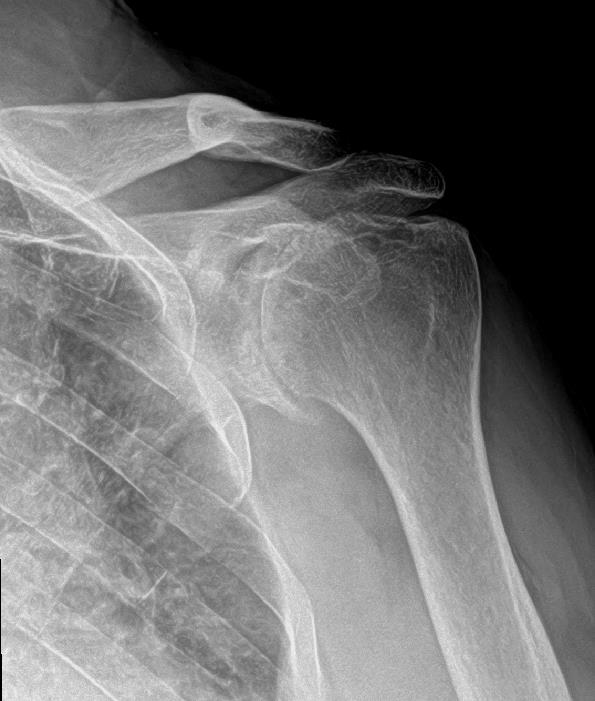

Glenohumeral Arthritis (Shoulder Arthritis) Shoulder & Elbow Manual Therapy For Glenohumeral Joint Therapeutic exercise is commonly used in the treatment and management of a range of shoulder disorders, is commonly advocated to address dysfunctions in mobility, posture, muscle activation, proprioception and strength and is supported by much research. The intent of this systematic review was to determine the effectiveness of manual therapy. The rehabilitation program focused on regaining stability and control of. Manual Therapy For Glenohumeral Joint.

Glenohumeral Joint Arthritis Putting Some Wear on the Tread The Manual Therapy For Glenohumeral Joint The rehabilitation program focused on regaining stability and control of muscles acting on the glenohumeral joint and scapulothoracic joints and gradually progressing the shoulder into functional positions and activities. Manual therapy stretching and joint mobilization are two essential treatment modalities when working on a client with frozen. The inclusion of manual therapy in standard comprehensive physiotherapy applied in the rehabilitation. Manual Therapy For Glenohumeral Joint.